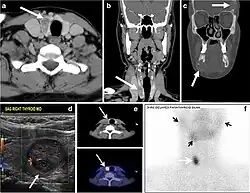

Fig. 4. A 45-year-old male patient presented with anterior mediastinal metastatic PTC lesions and occult primary on imaging. Histopathology examination of the resected thyroid gland revealed micro-foci of PTC; the largest, in the isthmus, measured 4 mm. a transverse greyscale ultrasound of the thyroid demonstrates homogeneous gland with normal echogenicity and size. No focal lesion or micro-calcifications. b Non-enhanced CT scan obtained as part of PET/CT examination shows a heterogeneous, large, relatively dense anterior mediastinal mass (white arrow) with peripheral calcification (arrowheads). Thyroid gland has normal CT appearance with no abnormal FDG uptake (not shown).[1] -